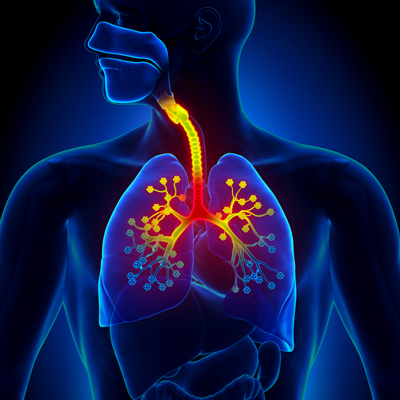

برونشیت چیست

برونشیت یا نایژهآماس به التهاب نایژهها در شش گفته میشود. این عارضه در اثر تورم نای یا نایژکها بروز میکند و به علت عفونت توسط باکتریها و ویروسها یا در اثر تحریکاتی مانند هوای آلوده و سیگار کشیدن ایجاد میشود.

برونشیت حاد یا مزمن، علائم متفاوت دارد. هنگامی که نایژهها ملتهب میشوند معمولاً انسداد نسبی راه تنفسی، سرفه و ترشح خلط رخ میدهد. در برونشیت حاد معمولاً سرفهها به مدت سه هفته به طول میانجامد.